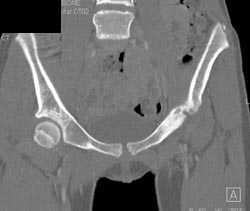

Diagnosis

3D of Implant